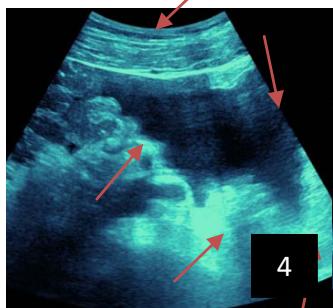

Iconography 1: 54-year-old patient with an intra-splenicsolid mass, anatomopathologically compatible with lymphoma: images 1 and 2: right pleurisy of moderateabundance, image3: celiacadenopathy, image 4: free ascites of moderateabundance, images 5 and 6: intra-splenicsolid mass of around $1418.16\mathrm{ml}$ in B mode and elastographyshowing areas of tumourrigidity, images 7-10: oblique linear images, showingbiopsy gun tracks.